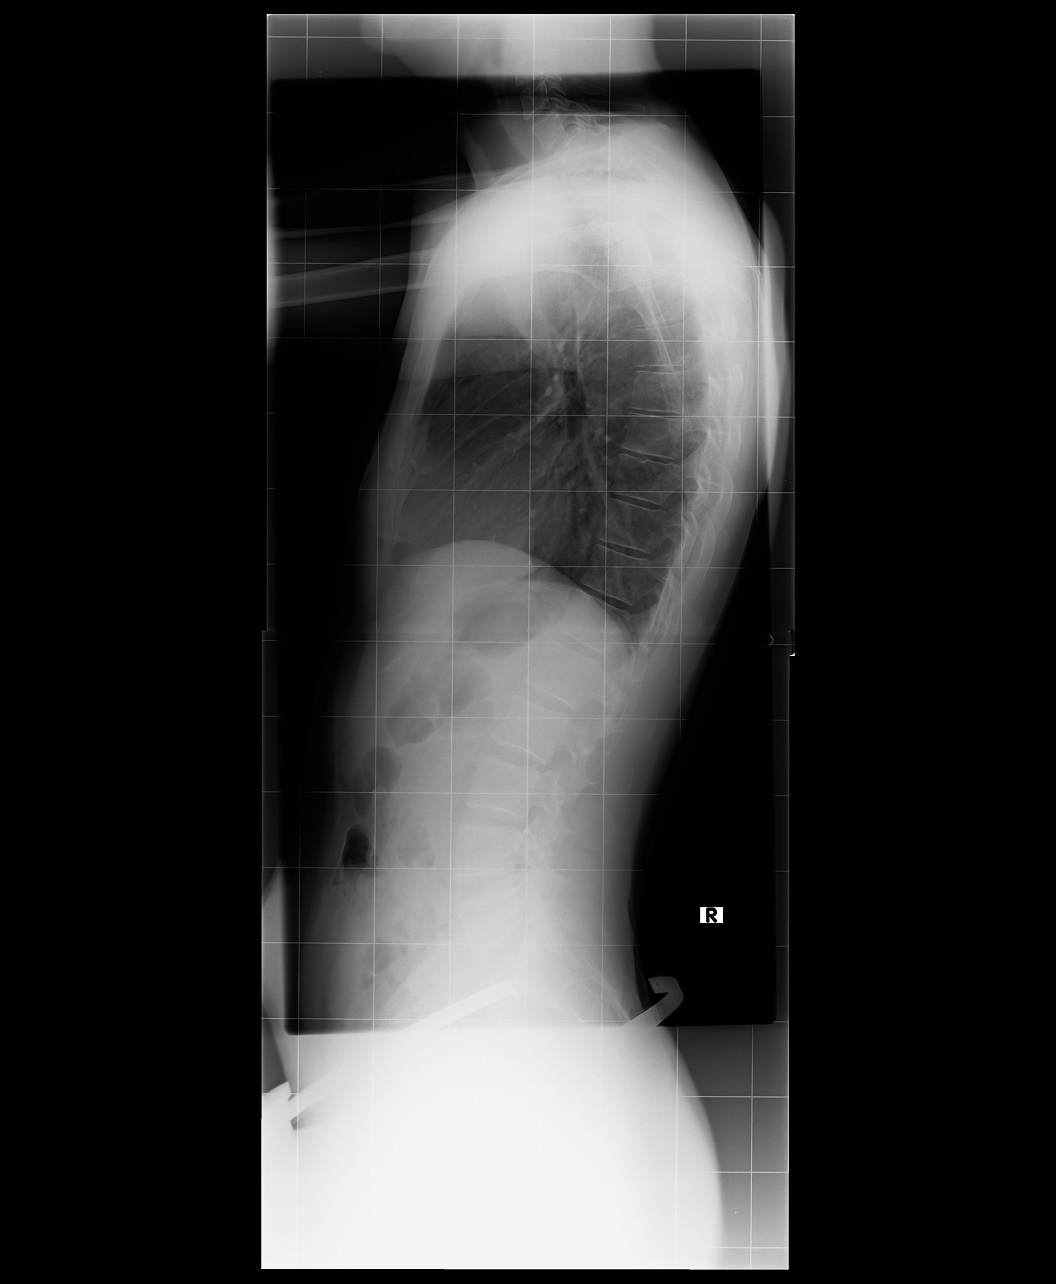

So ich hänge mal das Bild

meiner Wirbelsäule an.

Auf dem Bild sieht man die Hws sogar halbwegs.

Ergebnis vorher 59 Grad mit Korsett 36 Grad.